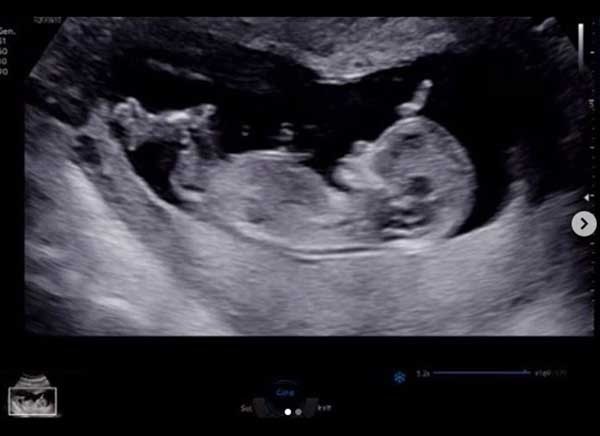

앞서 지난 4월 김영은은 자신의 인스타그램에 "골든이는 아...들배가 뭉쳐서 1주일 만에 다시 찾은 병원. 이 녀석 엄마한테 너의 존재감을 알리려고 그런거니? 왠지 아빠 판박이로 태어날 거 같구나 다들 딸로 알고 계셔서 잘못된 정보 정정합니다?♀? #16주#황금돼지맘#아들#뱃속에서부터#밀당하네#짜시기#아빠가자길닮았나보다고하던데#골든아빠화이팅#내일도승리하세요무적?"라는 글과 함께 초음파 사진을 올려 누리꾼들의 이목을 모은 바 있다.